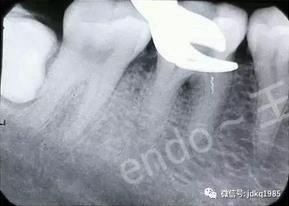

顯微鏡下在根管口可見斷針上端

應(yīng)用專用的“取斷針”器械盒,在顯微鏡輔助下建立直線通路,游離斷針